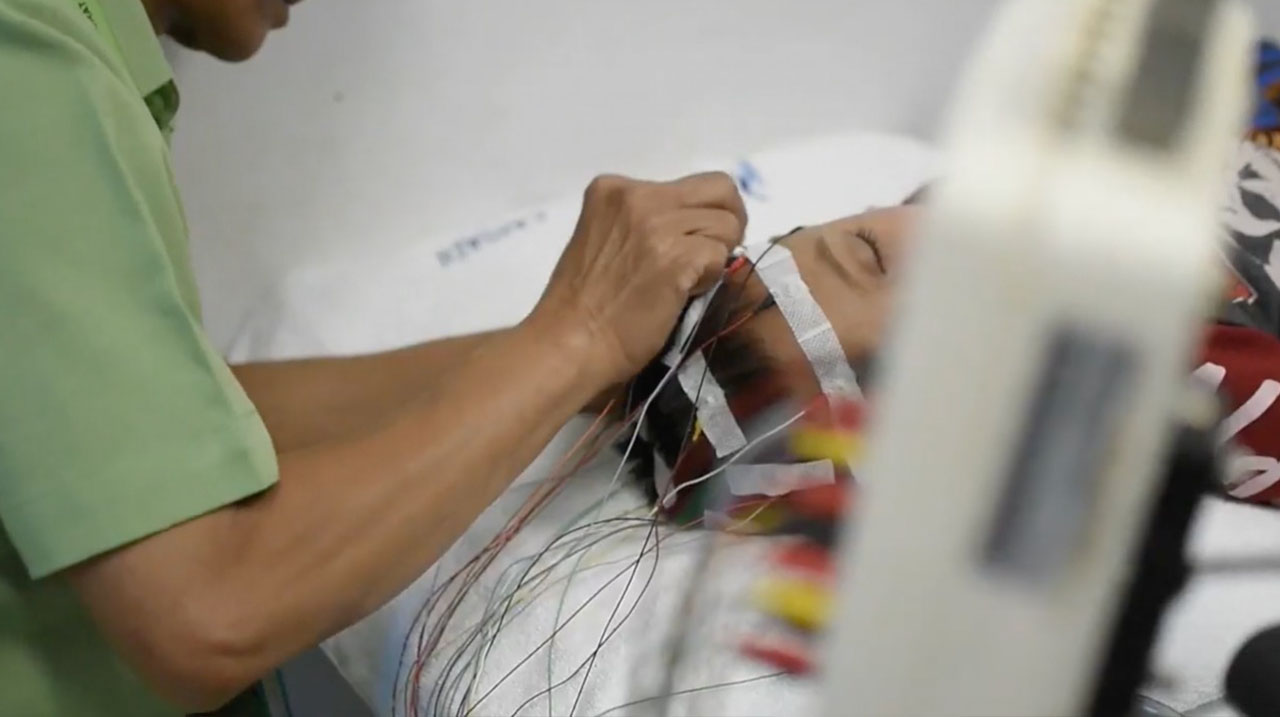

ELECTROENCEPHALOGRAPHY (EEG)

ELECTROENCEPHALOGRAPHY (EEG)